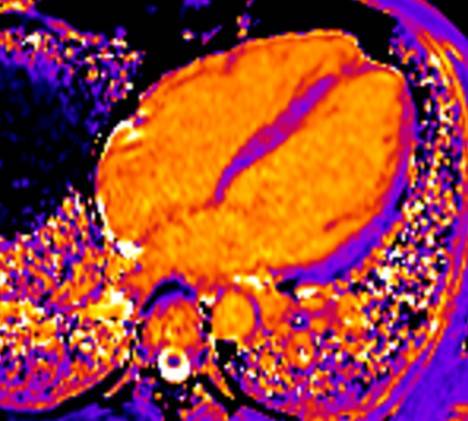

Die kardiovaskuläre MRT, auch Kardio MRT genannt, ist eine Magnetresonanztomographie des Herzens. Das bildgebende Diagnostikverfahren ermöglicht die detaillierte Darstellung des Herzens und des umliegenden Gewebes. Die Kardio MRT zeigt mögliche Herzerkrankungen, Funktions- und Fehlfunktionen, sowie den Grad der Herzgesundheit.

Die kardiovaskuläre MRT, kurz Kardio MRT genannt, ist ein Bildgebungsverfahren, dass mithilfe der MRT das Herz präzise scannt. Die entstandenen MRT-Bilder des Herzens sind detailliert und ermöglichen eine genaue Beurteilung und Befundung Ihres zuständigen Radiologen oder Ihrer zuständigen Radiologin.

Durch die Kardio MRT ist es möglich, verschiedene Aspekte Ihrer Herzgesundheit zu erfassen, darunter: Struktur und Form von Herzgewebe, Funktion und Lebensfähigkeit von Herzgewebe, Bewertung und Messung von Herzfunktionen und Blutflussanalyse der Herzgefäße.